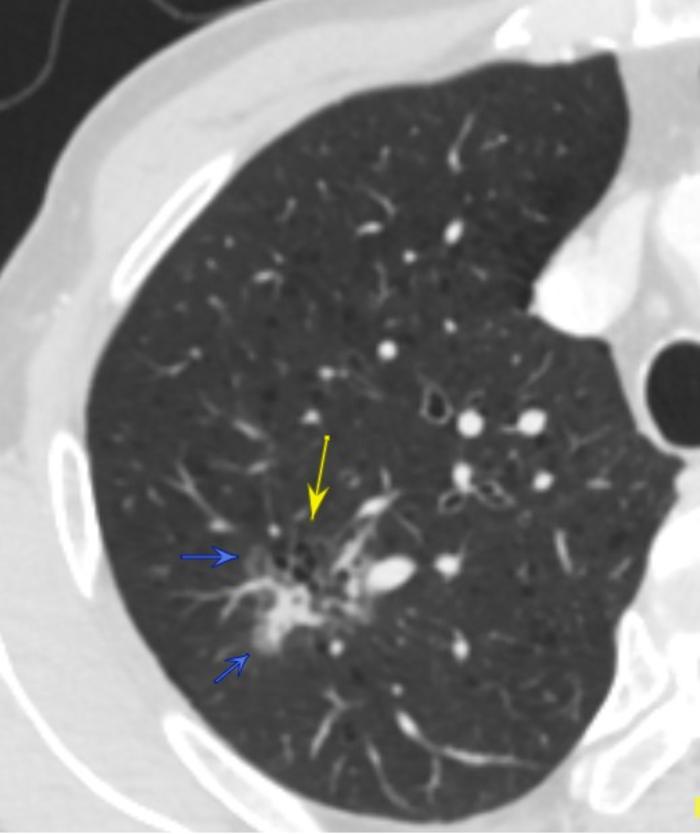

病例1:磨玻璃结节内部为蜂窝状结构

内部蜂窝状结构

这两张CT是同一个患者的混合磨玻璃结节,28×23毫米。第一张照片的黄色箭头可见边缘长毛刺影。第二张照片的两个蓝色箭头指示的是磨玻璃结节的灰色边缘,就是结节的磨玻璃成分。发白的部分是结节的实性成分。两张图内部可见蜂窝状磨玻璃成分。

病理是浸润性腺癌,两种亚型较好。